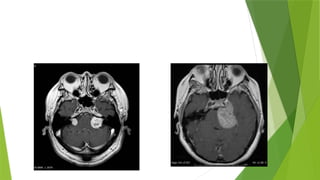

 An ill defined extra axial altered signal intensity mass lesion

noted arising from left trigeminal nerve extending along its

course with ganglionic and post ganglionic component.

 Superiorly it is compressing left optic nerve and optic chiasma

anteriorly extending into bilateral posterior ethmoid air cells

pushing posterior wall of left maxillary sinus anteriorly and

causing proptosis of left eye ball

 Posteriorly extending up to the level of interpeduncular cistern

compressing left sided midbrain and pons towards opposite side.

 Returning signals are iso intense on T1 and T2 and showing avid

enhancement on post contrast images and no restriction on DWI.

MRI FINDINGS  Anill defined extra axial altered signal intensity mass lesion noted arising from left trigeminal nerve extending along its course with ganglionic and post ganglionic component.  Superiorly it is compressing left optic nerve and optic chiasma anteriorly extending into bilateral posterior ethmoid air cells pushing posterior wall of left maxillary sinus anteriorly and causing proptosis of left eye ball  Posteriorly extending up to the level of interpeduncular cistern compressing left sided midbrain and pons towards opposite side.  Returning signals are iso intense on T1 and T2 and showing avid enhancement on post contrast images and no restriction on DWI.